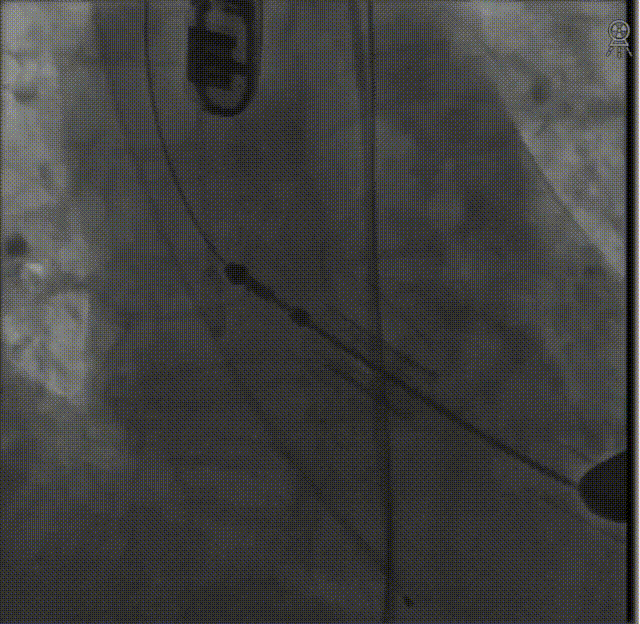

经股动脉送入猪尾导管,行根部造影:

定位件入窦后造影: